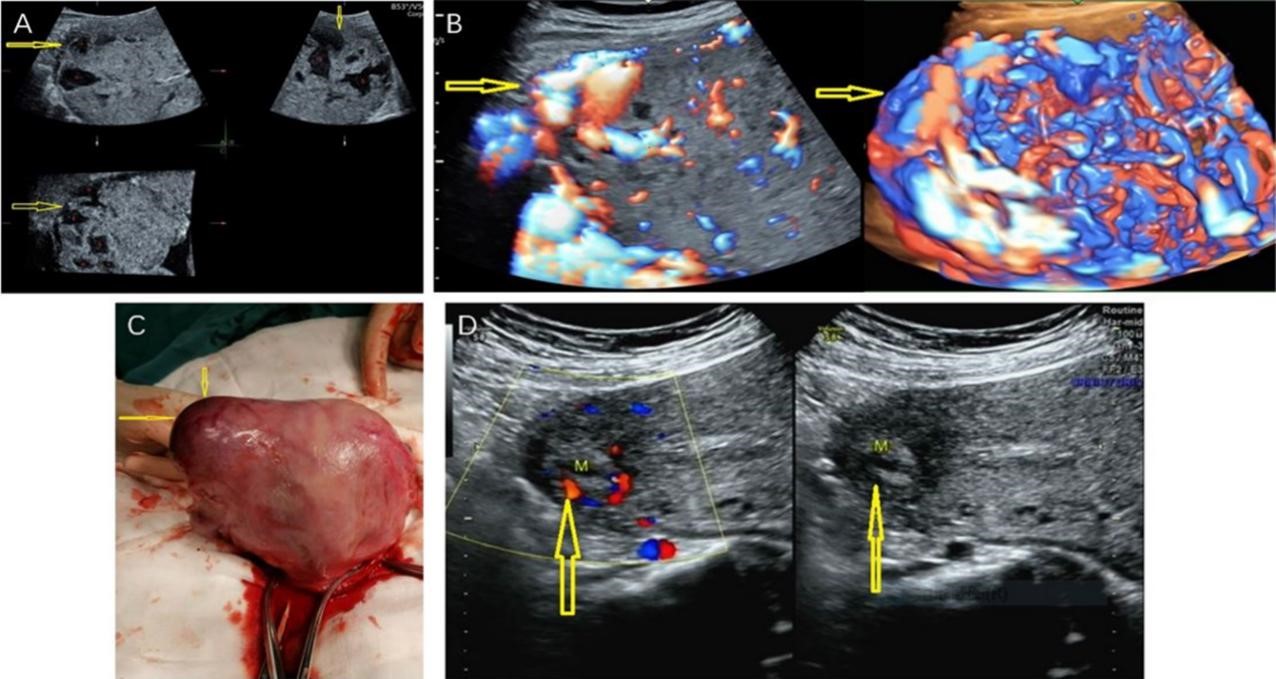

Fig. 5.The ultrasound images and intraoperative photos of a case of

type I angular pregnancy with placental penetration in the right angular. (A)

Multiplanar display of three-dimensional ultrasound at 32 weeks gestation. The

right uterine angular was slightly protruding; the thickness of the uterine

angular myometrium is 0 mm; the placenta is attached to the right angular, the

right wall and the upper right posterior wall; and there was no boundary between

the placenta and the muscle wall. Placental thickening with multiple lacunae and

eddy current is noted (The yellow arrow indicates the disappearance of the

normal muscle wall in the right angular with the placental tissue reaching the

serosal layer and the red pentagram indicates multiple lacunae in the placenta).

(B) Three-dimensional HD-Flow at 32 weeks of gestation (There are abundant and

messy blood flow signals in the placenta and under the serosa of the placenta

with the yellow arrow indicating that the type of blood flow in the right angular

overflows the serosa). (C) A photo of uterus during low transverse uterine

segment cesarean section (The yellow arrow indicates a 50.0 mm

In our study, a 31-year-old pregnant woman with a type I angular pregnancy had a

previous live vaginal delivery 10 years prior without complications or other

surgical history. She was diagnosed as having a normal intrauterine pregnancy

during the first and second trimesters at another hospital. At 32 weeks

gestation, ultrasound determined that the fetus had hydrocephalus and placental

penetration at the uterine angular (Fig. 5A,B). The MRI scan confirmed the

ultrasound examination findings. After informing the patient of these findings,

she requested an induction of labor. Potassium chloride was injected into the

fetal heart under ultrasound guidance and a stillborn fetus was delivered by a

low transverse cesarean section. The placenta and fetal membranes were manually

removed. The right uterine angular demonstrated a 50.0 mm